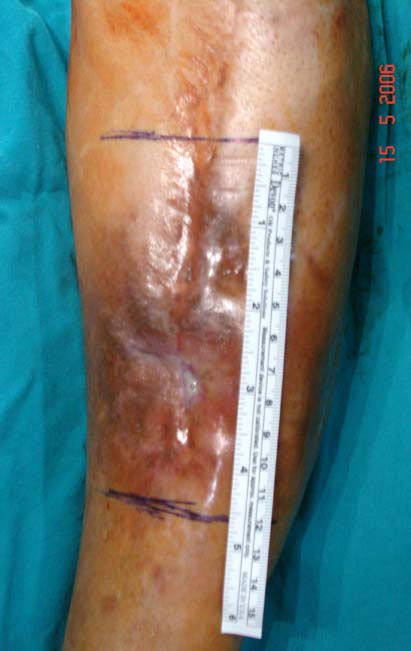

Kronik osteomiyelit, kemik ve yumuşak dokularda nekroza yol açar. Ölü kemik, patojen mikroorganizmalara ev sahipliği yapan bir nidus oluşturur. Konağın savunma sistemleri, mikroorganizmalarla baş etmek için sıklıkla optimal koşullarda değildir. Dolaşım bozukluğu yüzünden enfeksiyon bölgesine antibiyotikler yeterince ulaşamaz. Bu nedenle ölü dokuların ortamdan tamamen uzaklaştırılması gerekir (radikal debridman).

Uygun radikal debridman tüm nekrotik kemik ve yumuşak dokuların çıkartılmasını gerektirir, ve sıklıkla uzuvda instabiliteye neden olur. Kalan kemik ve yumuşak doku defektinin bir şekilde fiksasyonu ve rekonstrüksiyonu gereklidir. İlizarov’un ortaya koyduğu distraksiyon osteogenezi yöntemi, kaynamanın elde edilmesi, deformitenin düzeltilmesi, bacak boy eşitsizliğinin giderilmesi ve segmental defektlerin rekonstrükte edilmesi için başarıyla kullanılmaktadır.